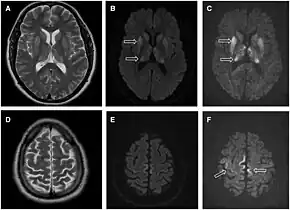

![]() | |

| Magnetic resonance image of sporadic CJD[2] | |

- MRI with diffusion weighted inversion (DWI) and fluid-attenuated inversion recovery (FLAIR) shows a high signal intensity in certain parts of the cortex (a cortical ribboning appearance), the basal ganglia, and the thalami.[36] The most common presenting patterns are simultaneous involvement of the cortex and striatum (60% of cases), cortical involvement without the striatum (30%), thalamus (21%), cerebellum (8%) and striatum without cortical involvement (7%). In populations with a rapidly progressive dementia (early in the disease process), MRI has a sensitivity of 91% and specificity of 97% for diagnosing CJD.[43] The MRI changes characteristic of CJD may also be seen in the immediate aftermath (hours after the event) of autoimmune encephalitis or focal seizures.[36]

Imaging

Imaging of the brain may be performed during medical evaluation, both to rule out other causes and to obtain supportive evidence for diagnosis. Imaging findings are variable in their appearance, and also variable in sensitivity and specificity.[46] While imaging plays a lesser role in diagnosis of CJD,[47] characteristic findings on brain MRI in some cases may precede onset of clinical manifestations.[48]

Brain MRI is the most useful imaging modality for changes related to CJD. Of the MRI sequences, diffuse-weighted imaging sequences are most sensitive.[49] Characteristic findings are as follows:

- Focal or diffuse diffusion-restriction involving the cerebral cortex and/or basal ganglia. The most characteristic and striking cortical abnormality has been called "cortical ribboning" or "cortical ribbon sign" due to hyperintensities resembling ribbons appearing in the cortex on MRI.[50] The involvement of the thalamus can be found in sCJD, is even stronger and constant in vCJD.[51]

- Varying degree of symmetric T2 hyperintense signal changes in the basal ganglia (i.e., caudate and putamen), and to a lesser extent globus pallidus and occipital cortex.[47]